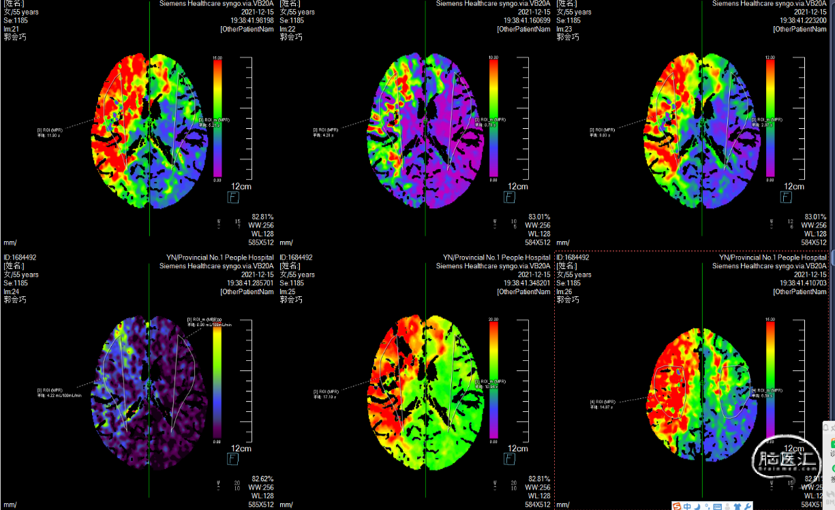

CTP

重要影像结论:头颈CTA右侧颈内动脉颅内段管腔闭塞。CTP提示有才大脑半球大片低灌注表现,梗死核心较小。

影像结论:右侧颈内动脉床突段狭窄完全解除。

影像结论:右侧半球脑灌注恢复。